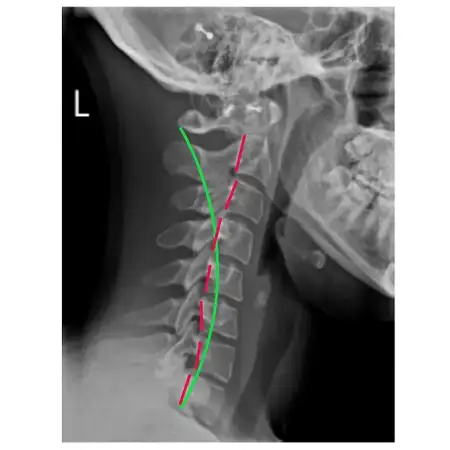

Think of your upper neck like a control center for your head and neck. The top two bones in your neck, called the Atlas (C1) and Axis (C2), are unique – they’re specially designed to allow your head to move freely in all directions. But here’s the critical part: This area is close to where your brainstem passes through, connecting your brain to the rest of your nervous system. When these vertebrae aren’t properly aligned (what we call an upper cervical subluxation), it can create a ripple effect throughout your body.

It’s like having a kink in a garden hose – when these bones are subluxated (blocked or misaligned), they can create interference on nerves, affect blood flow to your head, and create tension in your neck muscles. This disruption often leads to different types of headaches, including: